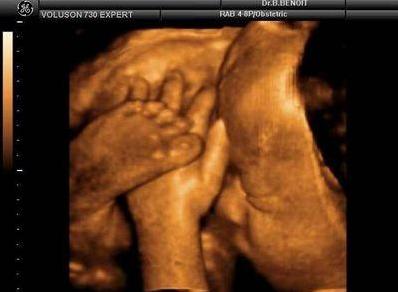

“四维彩超”——超声影像对于优生极其关键,可不少宝妈会遇到一种尴尬的情况,也让医生很头疼,那便是胎宝宝老趴着,基本上看不到五官及表情。

有位孕妈今天来我院做四维,小宝宝一点不“配合”,医生说脸没转过来看不到面部特征,所以只能出去溜达会儿再来照,溜达了半个小时再回来照,小家伙还是挡住脸。

一上午折腾了三次,宝宝都是用手捂住脸。孕妈被折腾坏了,真是欲哭无泪啊!

像这种情况,相信不少孕妈们都遇到过,给小家伙照个四维可真不容易呢!